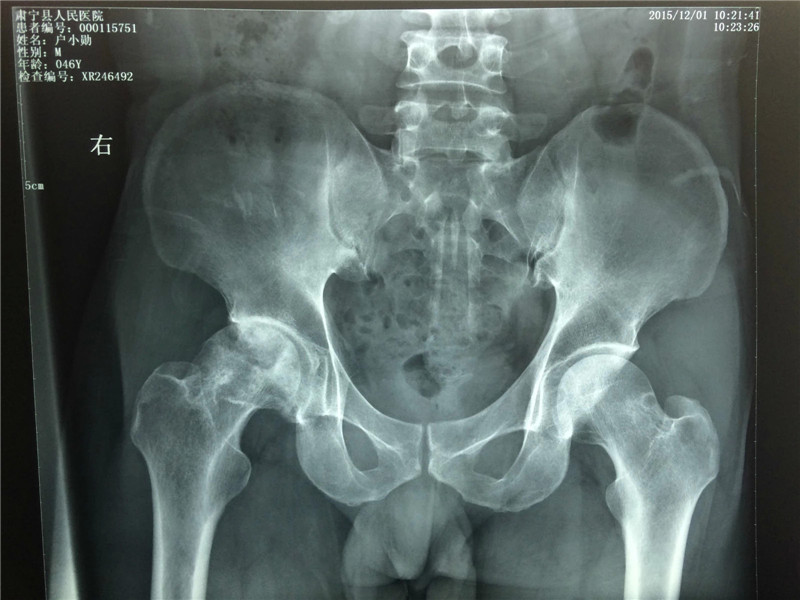

经过4个月的治疗:疼痛症状减轻,塌陷状况改善,骨质恢复

经过治疗后,户先生感觉治疗效果很好,带药回家治疗。